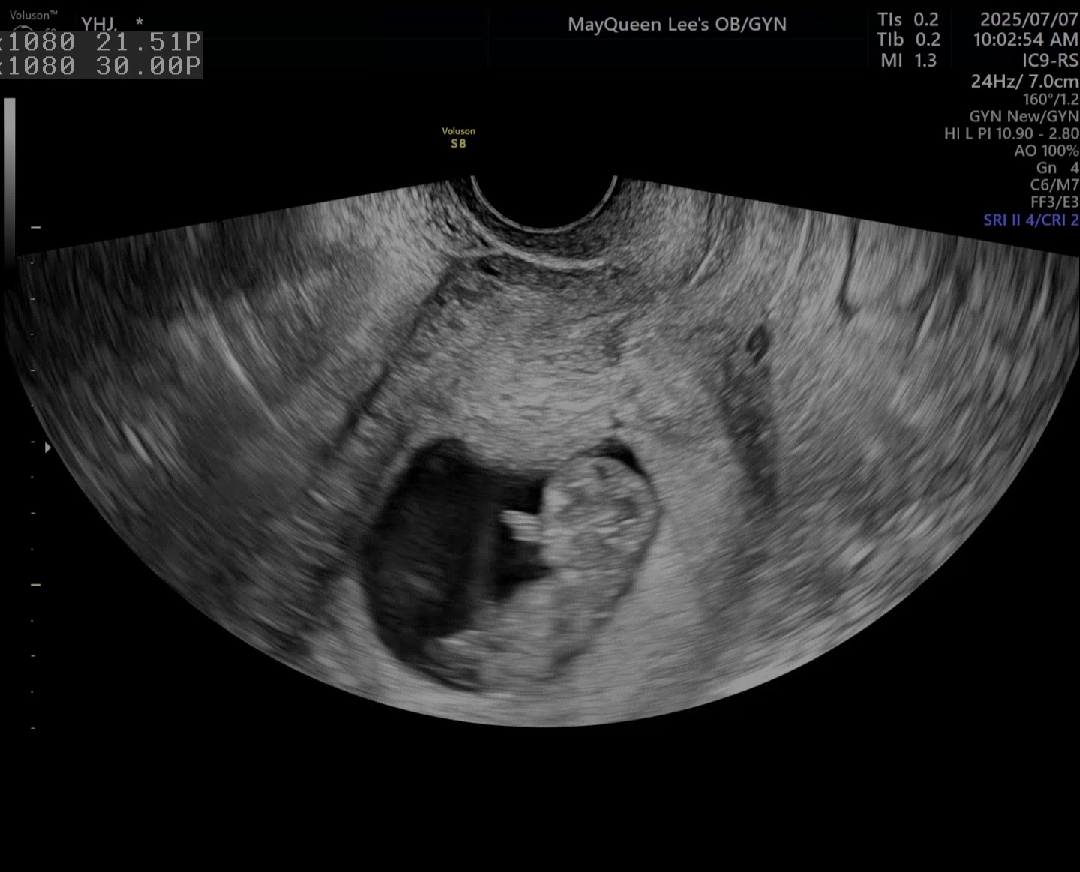

저는 오늘 10주2일 딱풀이가 꼬물꼬물 노는걸 보고왔어요~ 항생제 치료를 계속 하는 중이라서 꼬물꼬물 잘 노는 아이를 보니 너무 기쁘고 미안함이 컸어요 아기가 꼬물꼬물 잘 놀고있다고 원장님이 좋아하셨어요 ㅎㅎ 다른 예비맘님들은 언제 태아 노는걸 보고 오셨나요??